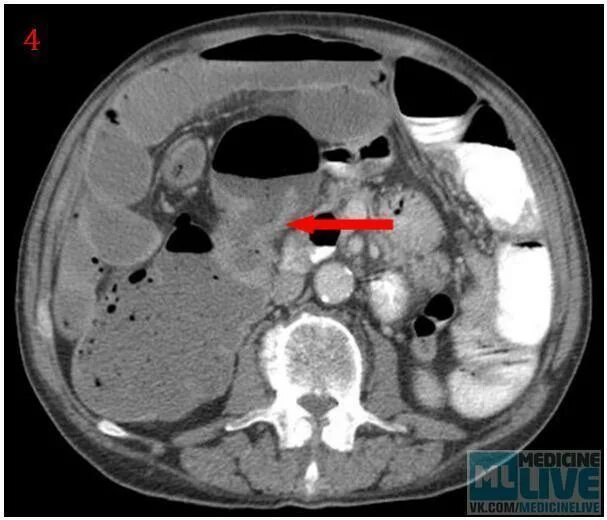

Метастазы при раке сигмовидной кишки